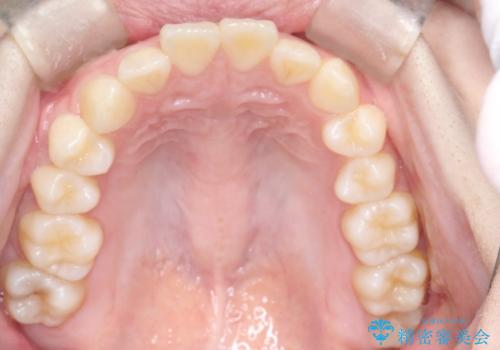

上と下の前歯がずれているため、抜歯を行い前歯の真ん中を合わせる治療計画を立ててワイヤー矯正にて治療を行いました。

途中、矯正用のアンカースクリューを使うことで、最終的にきれいに前歯の真ん中を合わせることができました。

2年という矯正期間でしたが、かみ合わせも良くなりを患者様には満足していただくことができました。